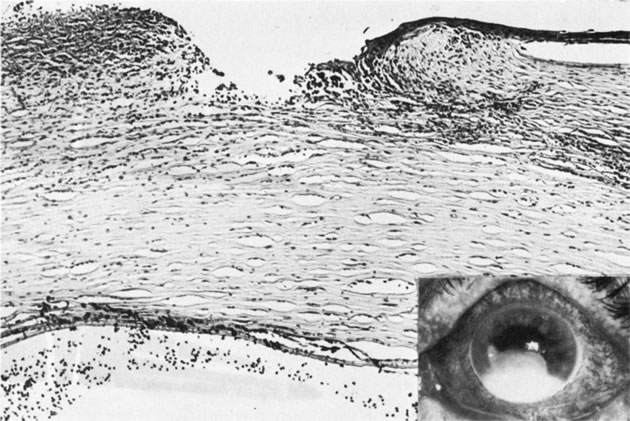

PETERS' ANOMALY

Peters' anomaly includes absence of central corneal endothelium, Descemet's membrane, and variable amounts of corneal stroma (Fig. 4). In most cases Bowman's membrane also is absent. Peters' anomaly may be caused by primary dysgenesis of the corneal endothelial mesoderm, primary dysgenesis of keratocyte and endothelial neural crest mesoderm, or secondary endothelial degeneration due to late anterior displacement of a normally developed crystalline lens.48 In addition, it has been suggested that abnormal apposition of an ectopic lens to the developing cornea during the second or third month of gestation may be the cause of exceptional cases of peripheral Peters' anomaly.49

Fig. 4. Peters' anomaly. A. Note the central corneal scar in the right and left eyes. The lens was adherent to the back of the corneal scar. Iris abnormalities also were present. B. The anterior segment shows a posterior corneal defect, a “top hat” appearance of the lens, and total adherence of the anterior surface of the iris to the cornea. C. High magnification shows termination of the endothelium and Descemet's membrane (arrow), corneal thinning, and localized absence of Bowman's membrane. The lens (lower left) is artifactually separated from the cornea. D. A PAS-positive membrane (lens capsule) is shown (top) adherent to the posterior corneal surface (arrow). The lens cortex (c) is artifactually separated from the rest of the lens (bottom). (Courtesy of SEI Photoarchives.) (B–D modified from Scheie HG, Yanoff M: Peter's anomaly and total posterior coloboma of retinal pigment epithelium and choroid. Arch Ophthalmol 87:525, 1972.)

Histopathologic findings include absence of Descemet's membrane, corneal endothelium, and usually Bowman's membrane, as well as thinning of corneal stroma. The defects in Descemet's membrane, although usually single and central, may be multiple and isolated to the periphery or may be limited to an area of adhesion of iris.56 Descemet's membrane has been found to have embryonal ultrastructural characteristics combined with attenuated endothelium.57 The corneal stromal lamella are more irregular and closely packed when compared with normal. Immunohistochemical markers indicate that a normal complement of collagens type I, III, IV, V, and VI occurs in Peters' anomaly; however, an increased concentration may occur of the adhesive protein fibronectin, which is known to play a role in the embryologic development of the cornea.58–60